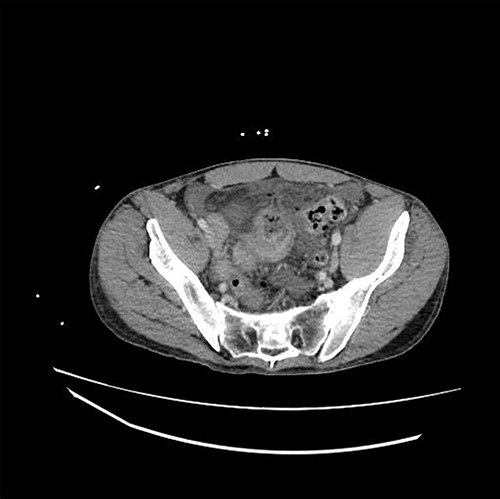

The patient is a 31-year-old male with medical history significant for EDS Type IV who presented for evaluation of sudden onset of abdominal pain, which woke him from sleep. He had a medical history significant of mitral valve prolapse and prior bacterial endocarditis resulting in bovine pericardial mitral valve replacement (MVR) on Coumadin, hemorrhagic left parietal stroke, history of ventilator dependent respiratory failure s/p tracheostomy and percutaneous endoscopic gastrostomy tube (PEG) with subsequent decannulation and removal. Current medications included aspirin 81 mg, warfarin, furosemide, Lisinopril, metoprolol and fluoxetine. Admission vital signs were unremarkable. Physical exam revealed a distended, diffusely tender abdomen with involuntary guarding. The lab values were significant of a leukocytosis of 18.53, INR 2.50 and lactic acid of 2.7. A computed tomography scan of the abdomen and pelvis with intravenous contrast demonstrated a dilated loop of distal ileum with associated mucosal thickening, free air and free fluid concerning for bowel perforation (Fig. 1).

CT demonstrating thickened loop of ileum in the pelvis with pneumoperitoneum and free fluid.